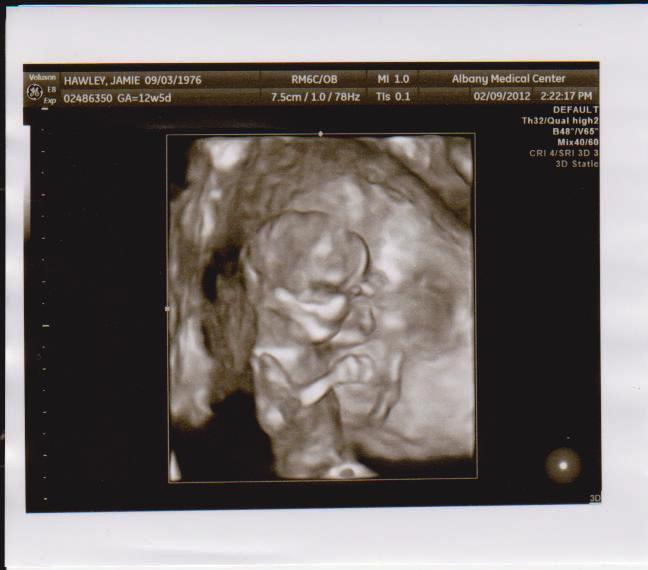

Great Expectations A 4d Ultrasound Experience Albany Georgia